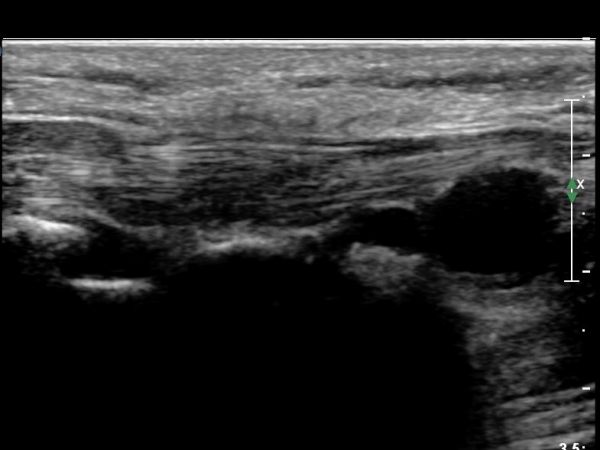

4 sono.jpg

¼Õ¹Ù´Ú ºÎÀ§¿¡¼­ ô°ñ½Å°æ ½ÉºÎ °¡Áö º´Áõ

(periphral neuropathy  of  deep palmar branch of ulnar nerve at palm level).